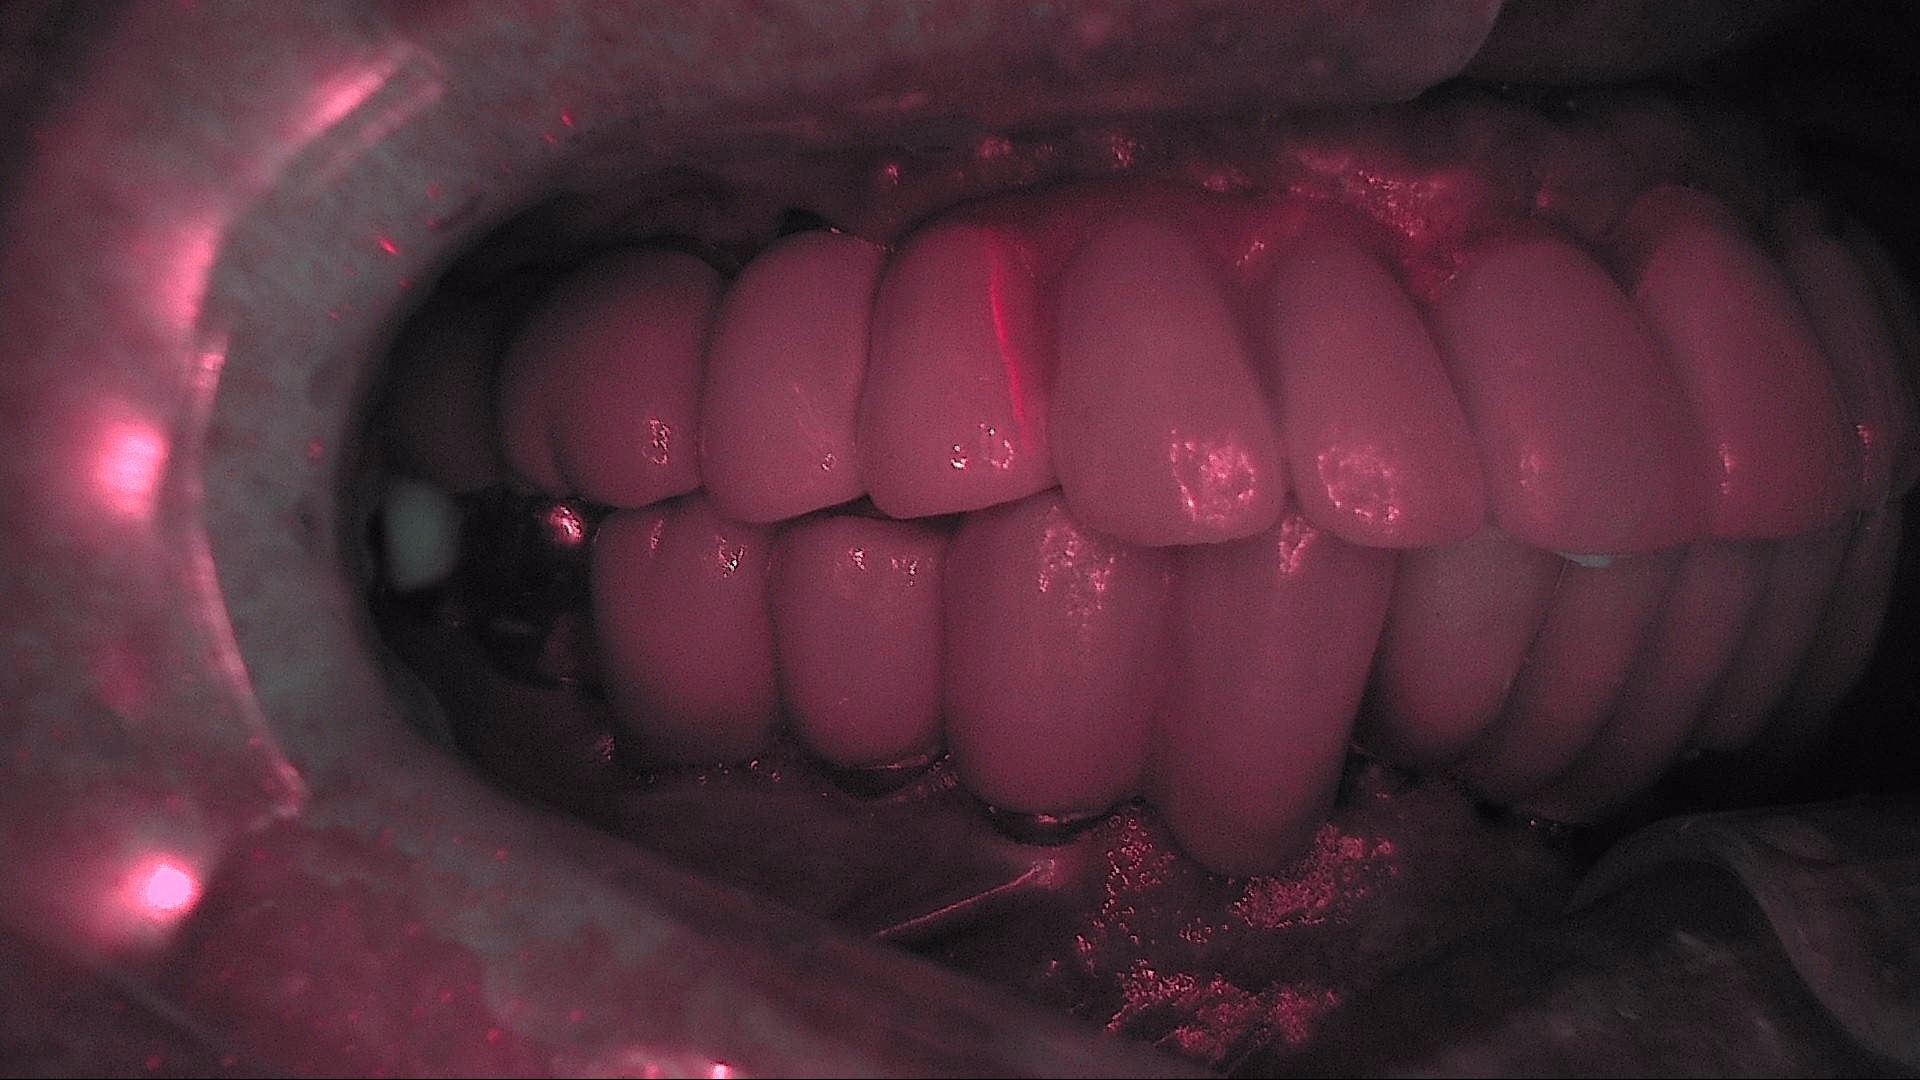

Crack

큐레이캠프로, 큐레이펜씨